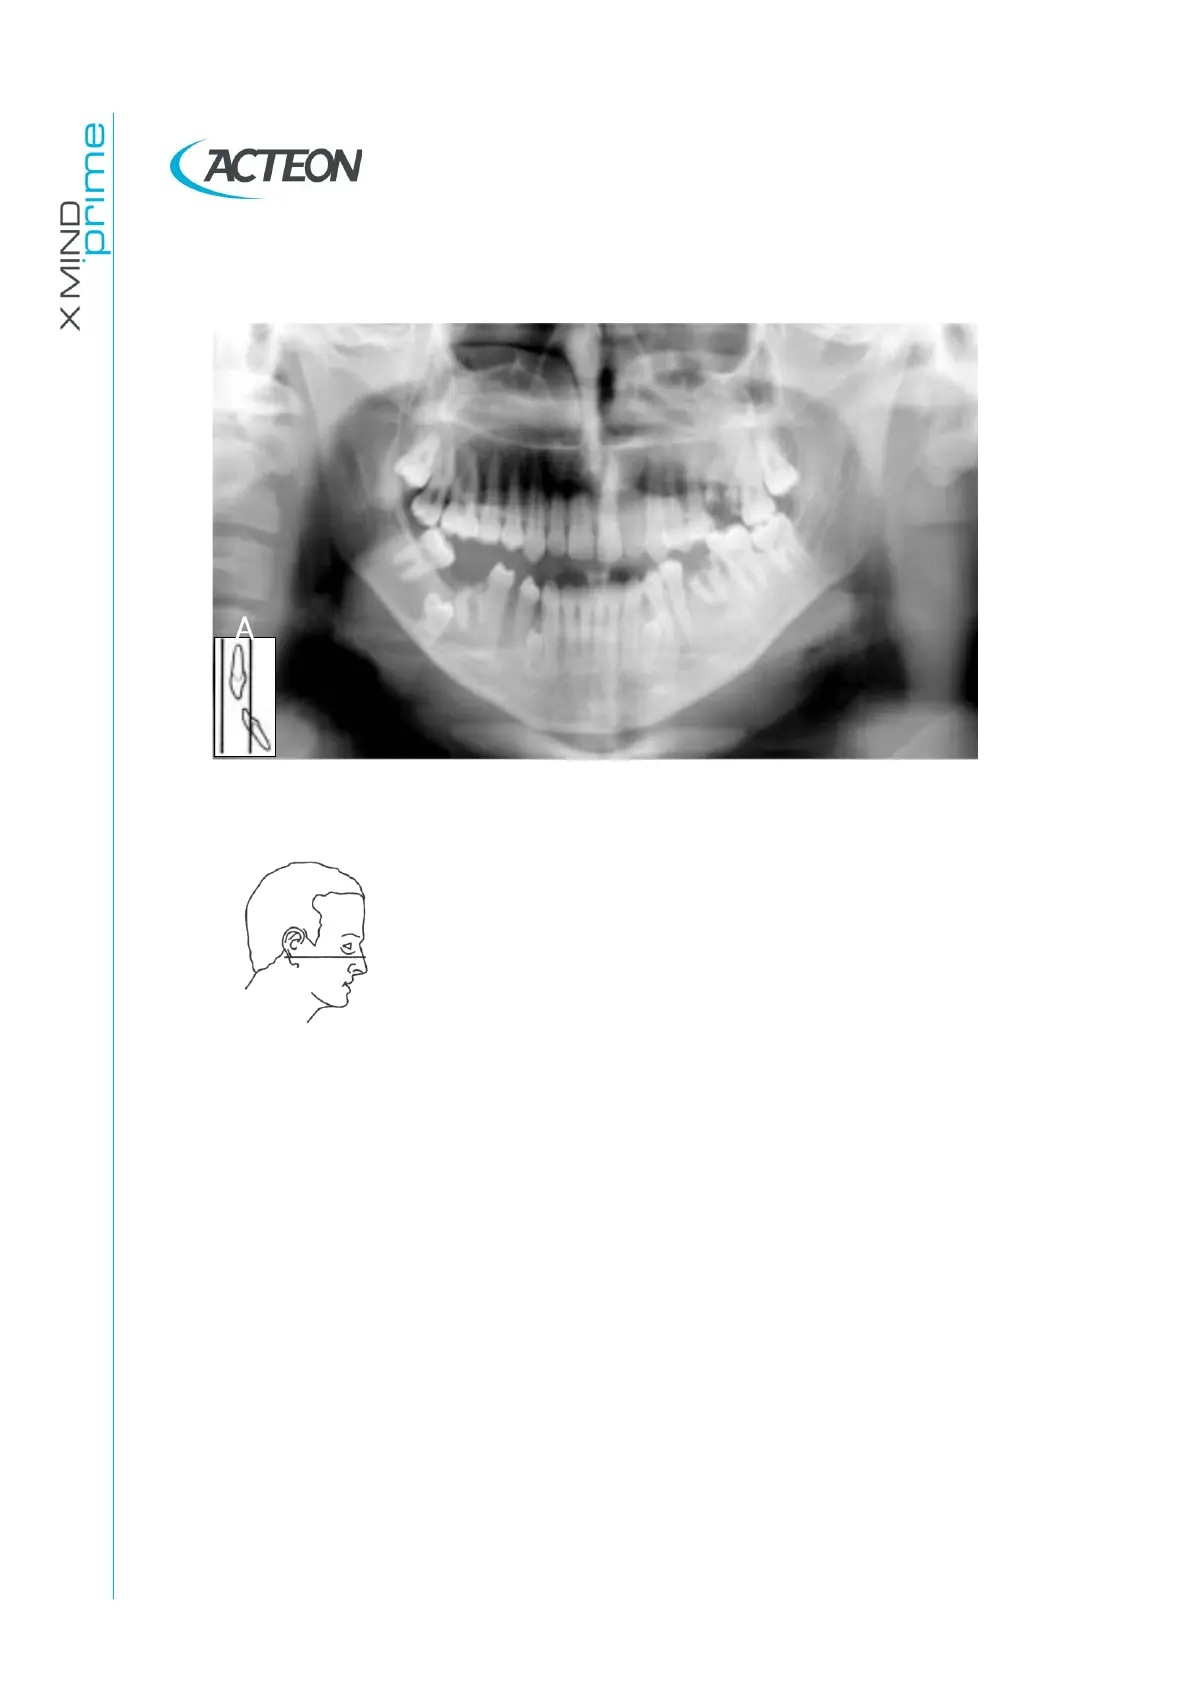

11.2.3 Downward angulation of the head

Figure 36

Problem

The Frankfurt plane is tilted downward.

Effects

The roots of the mandibular anterior teeth are positioned

outside the focal trough so it is out-of-focus and blurred.

The shadow of the hyoid bone is typically superimposed on

the anterior mandible.

Condyles may be cut off at the top of the radiograph.

Pre-molars are severely overlapped.

Severe curvature of the occlusal plane.